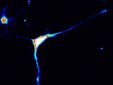

“Abbiamo utilizzato la tecnologia CRISPR/Cas9 per modificare cellule pluripotenti umane in coltura in modo da spegnere una delle due copie del gene, mimando così la situazione dei pazienti”, spiega la dottoressa Pavinato. “La parte più complessa dello studio è stato derivare dei neuroni da queste cellule, e studiarne la funzione in laboratorio”, continua la dottoressa.

Un approccio anche noto come “Malattia in provetta” o “disease in a dish”. La ricerca ha dimostrato che perdere una delle due copie di CAPRIN1 causa un’alterazione della organizzazione e della funzione dei neuroni, nonché della loro attività elettrica. L’importanza dello studio risiede, inoltre, nella definizione del ruolo biologico di CAPRIN1, in quanto è stato possibile dimostrare che regola la sintesi di molte proteine nei neuroni regolando l’espressione di molti geni nel cervello. CAPRIN1 è una proteina molto importante, quindi, uno snodo all’intersezione di numerosi meccanismi biologici dei neuroni, che permetterà di identificare numerosi altri geni associati a disordini del neurosviluppo.